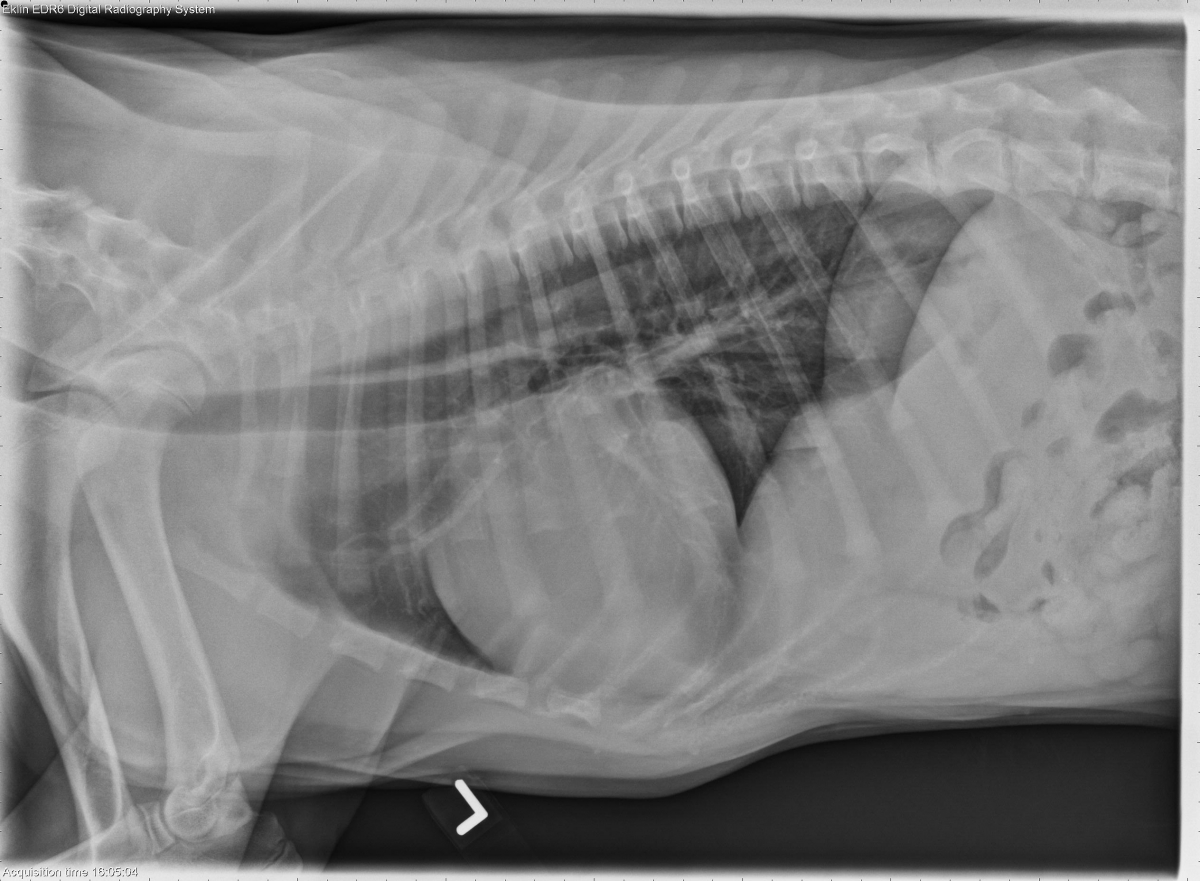

Today’s case is a 4 month old male Golden Retriever with episodes of panting at rest. What are your findings?

R LAT Thorax

The cardiac silhouette is moderately enlarged without specific chamber enlargement. The apex of the cardiac silhouette is not distinct from the diaphragmatic border. The pulmonary vasculature is normal. No abnormalities are seen in the pulmonary parenchyma, mediastinum, or musculoskeletal structures. There is mild cranial deviation of the gastric axis in the portion of the abdomen included.

• Congenital peritoneal pericardial diaphragmatic hernia.

• Several liver lobes and the gallbladder were confirmed to be in the pericardium by ultrasound examination.